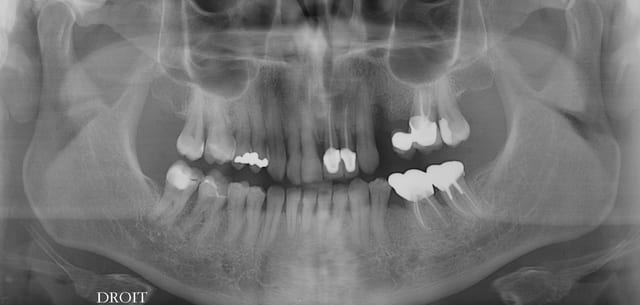

Je viens de revoir le patient et je peux vous apporter quelques précisions ainsi que des photos( désolé si la qualité n'est pas parfaite).

Patient de 45 ans, fumeur, motivé mais ne pouvant se payer d'implants.

Il a déjà vu plusieurs confrères qui lui ont proposé uniquement ( selon ses dires) une solution implantaire pour 12-11-21-22-23. Il souhaite du fixe...

En ce qui concerne la paro, la 12 est en mobilité stade 2, la 22 en stade 1 les autres étant non mobiles. Le sondage de 12 à 22 est de 3 mm, sauf en mésiale de 12 ( 6mm). La gencive est inflammatoire ( logique à la vue de l'inadaptation des couronnes, et des caries radiculaires).

Je pense lui proposer la solution du bridge avec 13,11,21,22, 24,25., même si la 13 est saine... Je prévoyais de reprendre l'endo de 22 mais la taille du tenon et sa longueur m'ont refroidi, peut être qu'une chir endo et obturation à rétro serait plus appropriées... Je prévois bien sur un surfaçage ainsi qu'un assainissement paro, une fois le bridge provisoire en place.

Tu as surtout un gros chantier paro à gérer. Et je ne pense pas que le tenon de la 22 soit si difficile à descendre, accessoirement l'endo de la 11 est aussi à revoir ( et là le tenon semble plus maousse ).

Essai de tout déposer, et améliore les endos, puis provisoires issues d'un wax-up pour simuler l'esthétique , ajuste ça comme il faut et attaque toi a la paro et à l'hygiène déplorable de ton patient......pas de traitement si pas d'hygienne.... Alors des implants dans ces conditions c'est suicidaires.